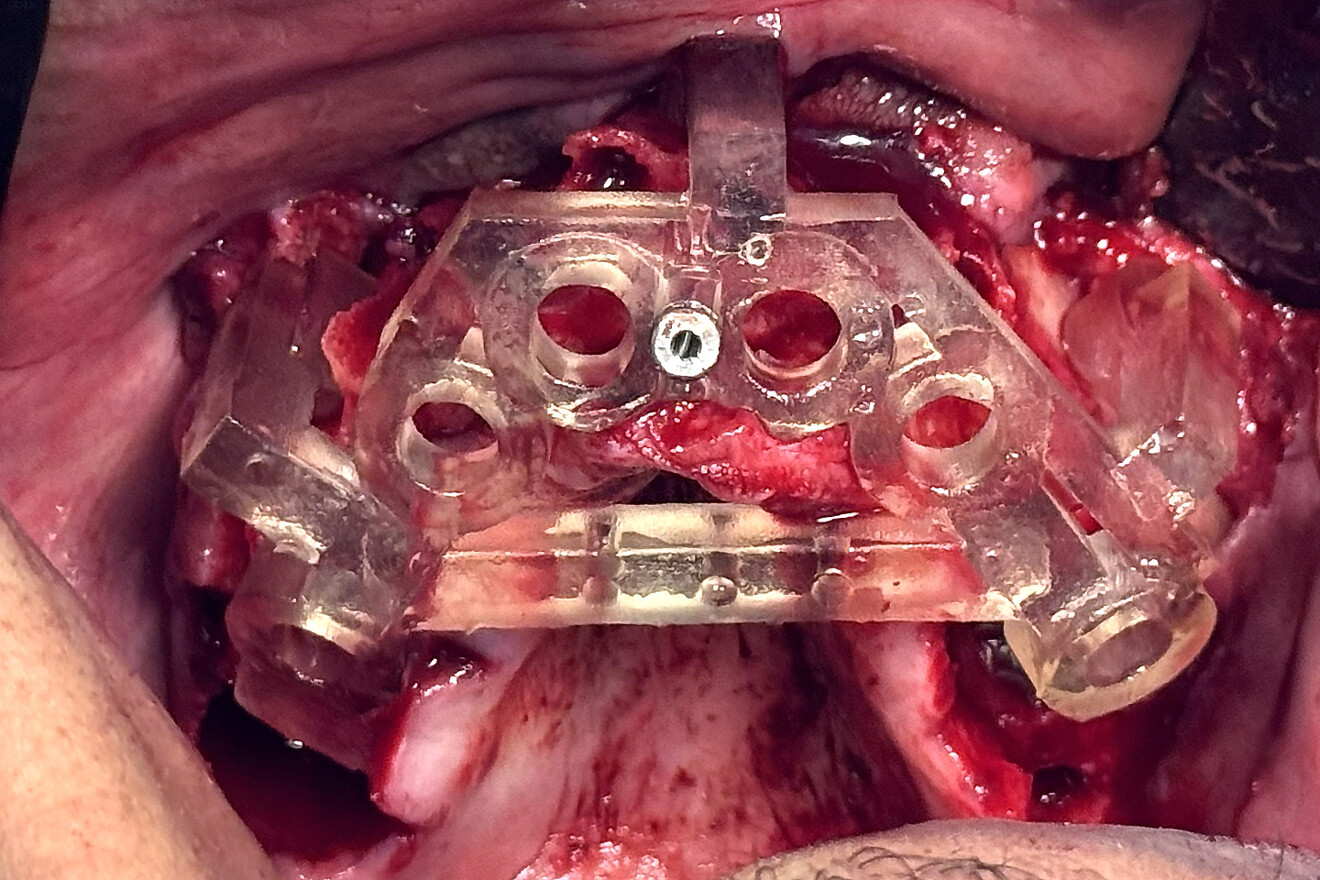

Fig. 11a: Retracted view of the nasopalatine canal pin guide seated on the maxillary bone with a single anchor pin to stabilise the guide.

The single 2 mm diameter nasopalatine canal anchor pin was placed with finger pressure until resistance was felt (Fig. 11a). Light taps with a surgical mallet allowed the pin to be fully seated, compressing the guide into the outer buccal bone. Another unique feature of the guide was the horizontal stabilising bar connecting the right and left sides. The horizontal bar contained specifically placed holes that provided slots for suturing the anterior palatal tissue, keeping it away from the osteotomy sites (Fig. 11b). The anterior implants were placed first, and guide stabilisers were secured to these implants to completely immobilise the guide, facilitating the posterior tilted osteotomy preparations. Through fully guided placement, the implants were delivered accurately as planned, providing the necessary support for the full-arch fixed restoration (Fig. 12).